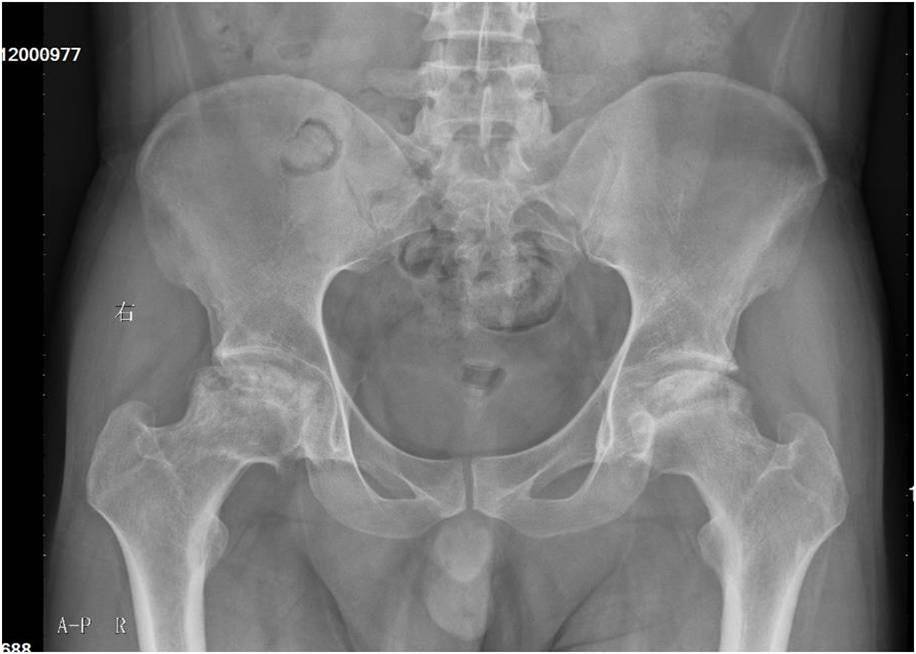

双侧股骨头缺血性坏死病历分享

于当地医院行双髋mri检查,诊断为"左侧股骨头缺血性坏死",药物治疗

和谐医患显真情—莱州市中医医院成功开展双侧股骨头缺血性坏死同时